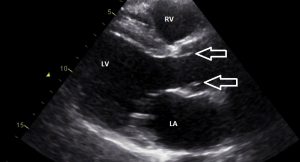

Een lange as opname laat een excentrische sluitlijn zien van de klep en een bolle “opgeblazen” configuratie van de kleppen tijdens systole (doming van de klepblaadjes).

Figuur 1: Hier zie je hoe de klep wat opbolt